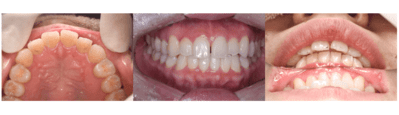

前歯の歯並びがきになる

| 年齢 | 20代女性 |

|---|---|

| 主訴 | 前歯の歯並びがきになる |

| 治療内容 | プチ矯正(上顎のみ) |

| 治療期間 | 2ヶ月 |

| 費用 | 165,000円(税込) (2022年2月現在) |

| リスク・副作用 | プチ矯正は全ての方に適応になるわけではありません。矯正中は器具が唇に接触するため口内炎ができやすくなります。歯が動かないなどで期間が長くなることもあります。 スペースをつくるために歯を削ることがあります。 |

| 治療方針 | 以前マウスピース矯正をしていたが、後戻りで前歯がやや前方にでてきてしまっています。 上顎下顎ともにあともどりがあり、歯と歯の間に若干スペースができている。 患者の希望が上顎だけだったので、下顎はそのままで、上顎のみ矯正をすることとした。 矯正は基本的にはスペースを作るため歯を削ることが多いが、今回のケースではスペースを閉じるだけなので、歯を削らずに行う計画を立てた。 |

矯正相談

【担当医師所見】

前歯の隙間が気になってきたとのこと。

CRを充填するか、矯正を行うかで選んでもらった。

矯正はおよそ3〜4ヶ月くらい(保定含む)で終わること、変色などの審美的なことに今後悩まなくて良いことから、矯正を選択した。

矯正後は保定装置を入れることをに同意を得た。

保定装置は上顎は舌側ワイヤー固定だとカリエスになりやすいので、マウスピース型の予定で考えた。

ビフォーアフター写真

治療前

治療後